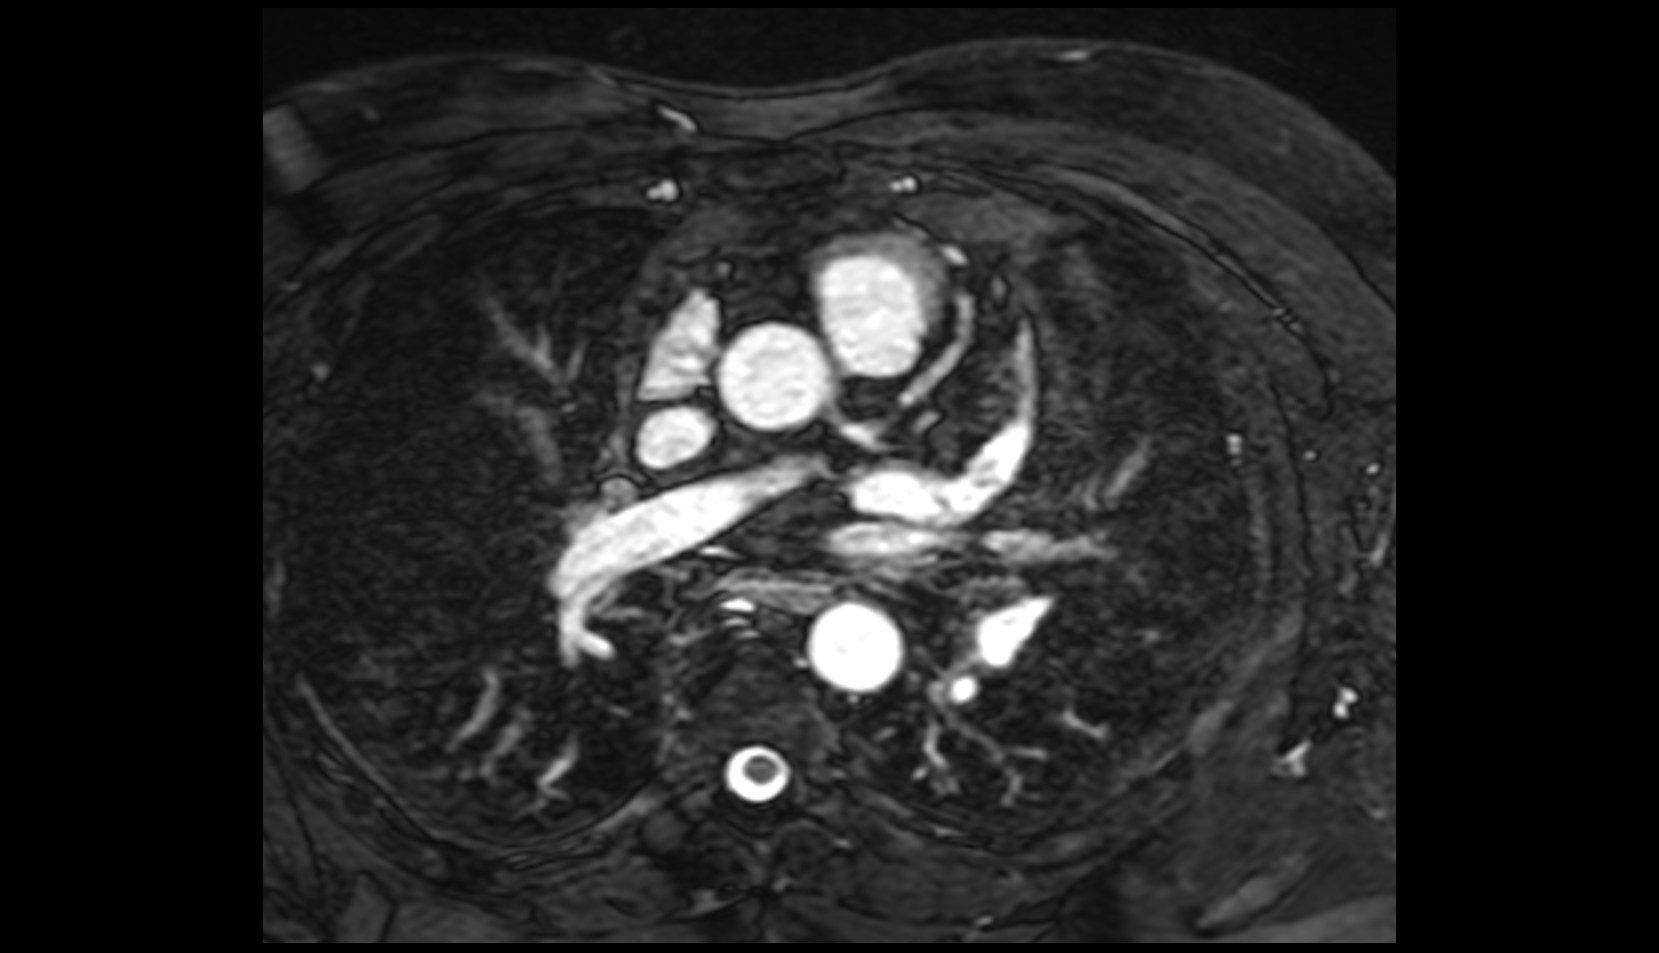

- Left anterior descending artery (LAD)

- Circumflex artery (LCx)

- Left main coronary artery (LMCA)

- Right coronary artery (RCA)